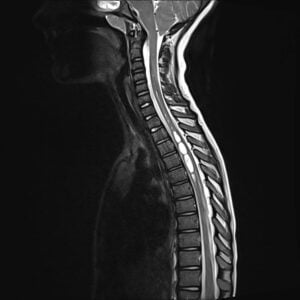

The treatment of asymptomatic CIM is largely conservative. Surgical treatment should be considered in patients with associated CIM headache symptoms impacting quality of life, large or enlarging syrinx, or objective abnormal neurological findings or myelopathy. The most common surgical approach is a cranio-cervical decompression. This involves removal of part of the occipital bone extending to foramen magnum, and may also include removal of posterior C1 arch, decompression with arachnoid opening followed by duroplasty (Fig 2&3). Other surgical options include bony decompression alone, of cerebellar tonsil coagulopathy or resection.

Figures 2 & 3. Preoperative and postoperative MRI T2 sagittal cervical spine. Preoperative image shows mild tonsillar ectopia with prominent cervical syringomyelia. Postoperative image shows adequate craniocervical decompression and significant reduction in cervical syringomyelia.